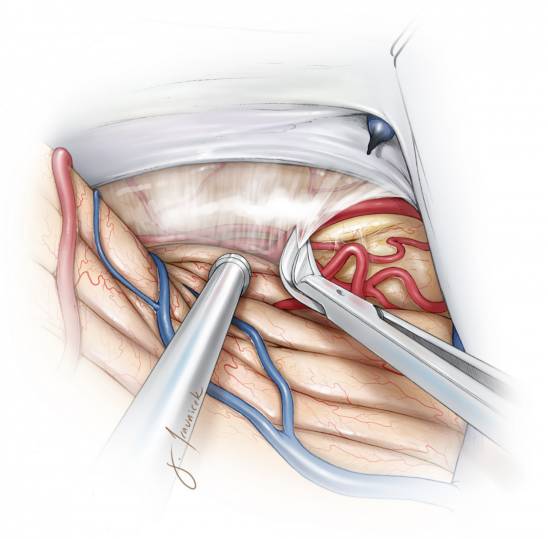

图6. 在切开天幕接近肿瘤的过程中,可通过锐性分离蛛网膜来充分暴露天幕游离缘的神经血管结构,早期的充分暴露能够避免在肿瘤切除过程中受到损伤。

图7. 识别天幕游离缘旁的滑车神经。将位于天幕缘旁的滑车神经及周围血管结构充分游离并保护起来,如果可行,先将这部分肿瘤减容。天幕游离缘附近的脑干背外侧神经神经血管结构要在大规模切除肿瘤之前充分暴露,以免切除过程中由于视野不清误伤。

图9. 在切除天幕游离缘的时候要注意保护滑车神经(上方插图)。若要沿着红色虚线切除将会损伤神经,而沿着黑色虚线则利于神经保护。另外,颞叶后方基底部的脑实质肿瘤需要T形切口切开天幕。切除左侧岩骨天幕区域脑膜瘤的术中图片证实了滑车神经在肿瘤和天幕前缘进入硬模(下图)。

图10. 在充分保护滑车神经的情况下,天幕切口可从岩骨边缘延伸直到中线以包含肿瘤基底区域。在少数情况下,如术中发现汇入天幕的枕叶引流静脉阻挡视野,可将其牺牲。沿中线切开天幕时必须注意保护直窦以及其分支。天幕有可能存在静脉湖,而天幕的静脉出血可以通过浸泡凝血脢的明胶海绵压迫止血,而双极电凝则会皱缩天幕,扩大裂口而加重出血。